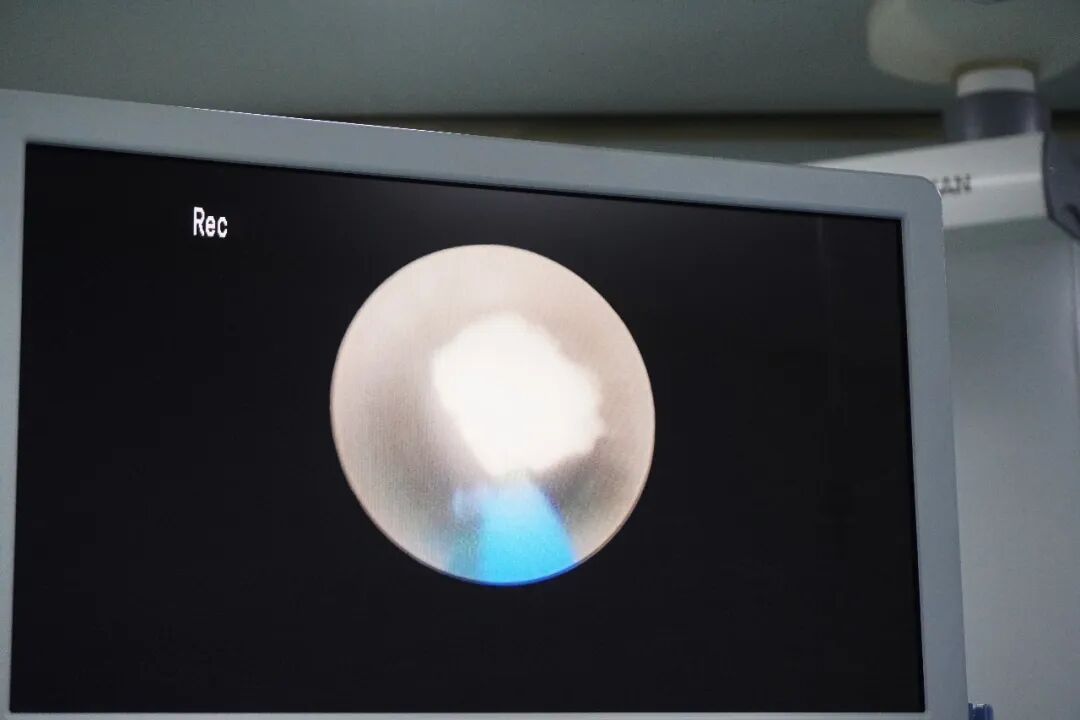

手术由经验丰富的医师团队操作。术中,医生将纤细的输尿管镜经尿道、膀胱轻柔置入右侧输尿管,精准抵达结石所在位置。在清晰的视频影像引导下,利用钬激光等先进能量平台将结石粉碎成细小颗粒,并通过器械将其取出。随后,为保障术后输尿管通畅、利于肾脏积水引流和黏膜修复,团队顺利置入了一根输尿管支架管。整个手术过程顺利,出血极少,有效解除了梗阻,保护了患儿的肾脏。

术前术后对比

成功解除病痛